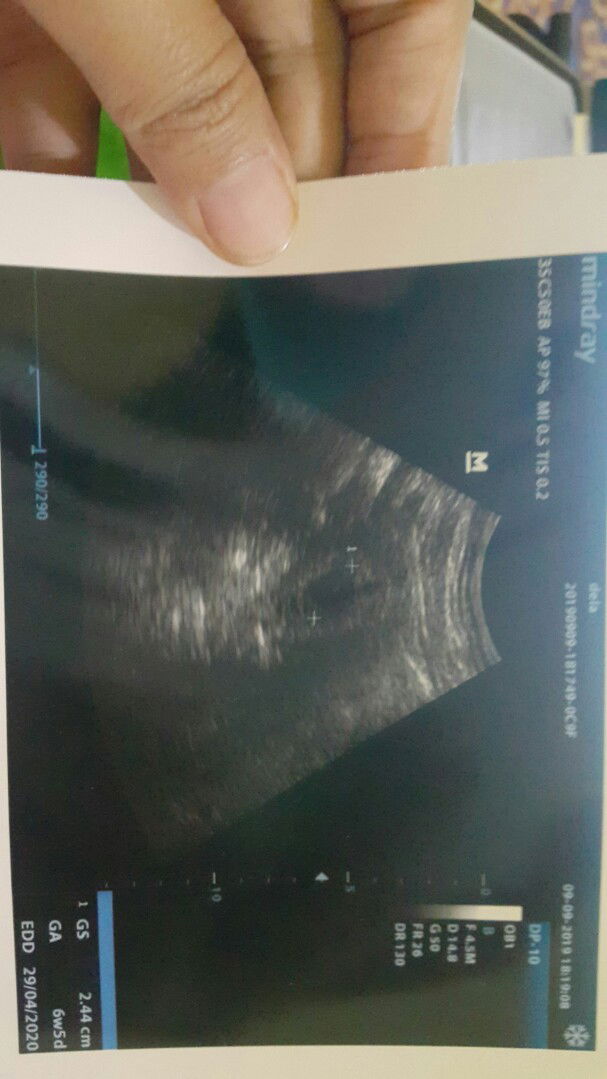

hamil muda dan flek

Asaalamualaikum bunda salam kenal.. Terimakasih sebelumnya sudah di perkenankan gabung di grup super ini.. Bun saya sedang hamil 6 minggu.. tapi beberapa kali flek dan keluar seperti jaringan berwarna hitam.. setelah itu usg alhamdulillah kantung janin masih ada.. apakah pernah ada yang mengalami flek saat TM 1 dan sehat sampai melahirkan ? Terima kasih bunda.. ini hasil usgku bun..janin belum terlihat